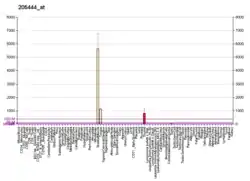

ATP2A1 SERCA pumps were very strongly down regulated in amyotrophic lateral sclerosis.[7]